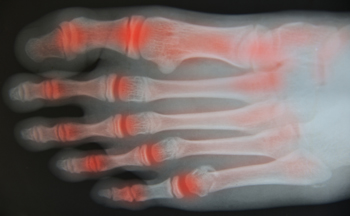

When Rheumatoid Arthritis Affects the Ankles

The synovial membrane is the protective tissue that surrounds joints such as the ankle. Rheumatoid arthritis is an auto-immune disease in which the body attacks this tissue causing it to become swollen and filled with fluid. Over time, this fluid can break the ankle joint down, causing it to become misaligned, deformed, and stiff. Other symptoms include ankle pain, fatigue, and fever. If the inflammation of rheumatoid arthritis goes unchecked, it may affect other parts of the body and lead to other diseases. While genetics can make you more predisposed to infections that may bring on rheumatoid arthritis, smoking, old age, and obesity may also increase your risks of contracting this disease. If you have pain in your ankles due to rheumatoid arthritis, a podiatrist may treat you with medications, physical therapy, orthotics, steroid injections or, in worst case scenarios, surgery to increase stability, reduce pain, and restore mobility in the ankles.

Because RA affects more than just your joints, including the joints in your feet and ankles, it is important to seek early diagnosis from your podiatrist if you feel like the pain in your feet might be caused by RA. For more information, contact Roy Moeller, DPM of Foot & Ankle Physicians West. Our doctors will assist you with all of your podiatric concerns.

What Is Rheumatoid Arthritis?

Rheumatoid Arthritis (RA) is an autoimmune disorder in which the body’s own immune system attacks the membranes surrounding the joints. Inflammation of the lining and eventually the destruction of the joint’s cartilage and bone occur, causing severe pain and immobility.

Rheumatoid Arthritis of the Feet

Although RA usually attacks multiple bones and joints throughout the entire body, almost 90 percent of cases result in pain in the foot or ankle area.

Symptoms

• Swelling and pain in the feet

• Stiffness in the feet

• Pain on the ball or sole of feet

• Joint shift and deformation

Quick diagnosis of RA in the feet is important so that the podiatrist can treat the area effectively. Your doctor will ask you about your medical history, occupation, and lifestyle to determine the origin of the condition. Rheumatoid Factor tests help to determine if someone is affected by the disease.